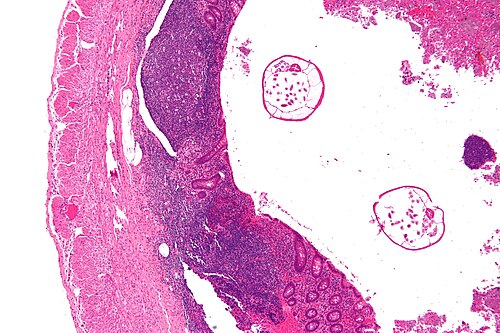

Provided clinical history

17 year old woman, appendicitis

Site

Appendix

Primary image

Very low magnification. H&E stain.

Appendix looked normal at time of surgery.

The abnormality is in the lumen.